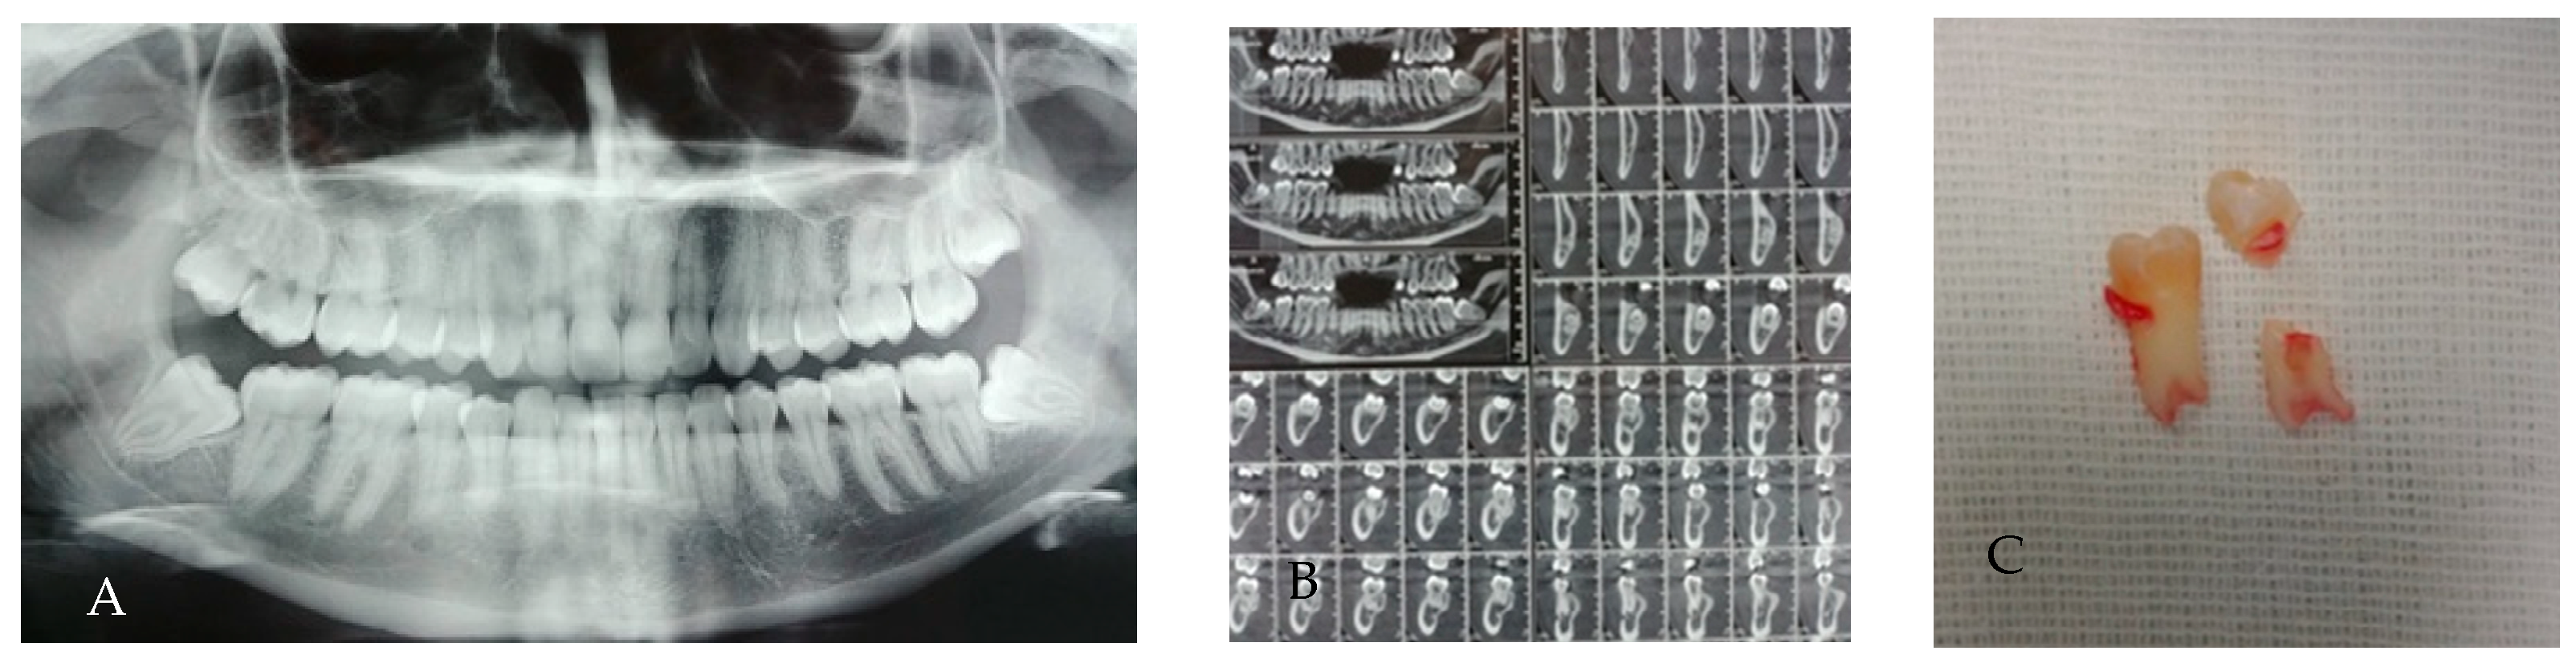

3.7. Dilaceration/Apical Curvature

3.8. Hypercementosis

- Club-shaped hypercementosis: root exhibits a generalized, smooth, thickened contour; extraction may be more difficult due to increased root diameter.

- Focal hypercementosis: localized nodular deposits on one or more aspects of the root; may create mechanical undercuts, increasing the risk of root fracture during luxation.

- Circular (or circumferential) hypercementosis: uniform thickening encircling the root, often leading to ankylosis-like resistance during extraction.